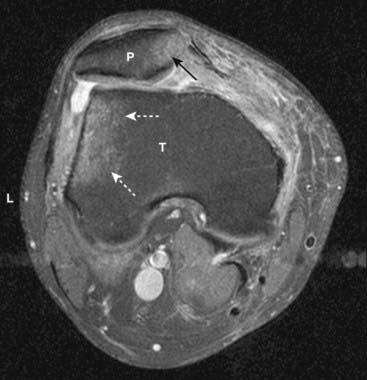

Figure 20-7 Bone marrow edema due to transient lateral patellar dislocation.

Axial proton-density, fat-saturated image (a T2-like sequence) demonstrates bright bone marrow edema involving the lateral (L) tibial (T) plateau (dotted white arrows) and medial aspect of the patella (P) (solid black arrow). This edema is due to recent lateral patellar dislocation with contusion of the patella as it struck the tibia.